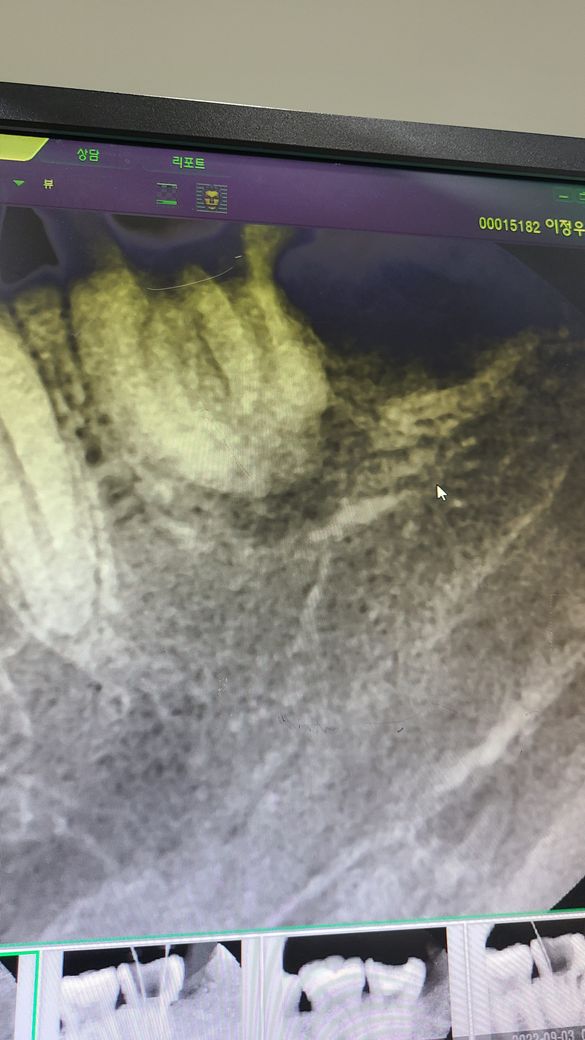

사랑니로 인하여 이미 앞쪽 어금니의 뿌리가 염증에 의해 녹은 상태입니다. 신경치료를 하더라도 예후가 매우 안 좋아 보이며 해당 부위의 어금니가 신경치료 도중 뿌리도 일부 부러진 상태입니다. 살려서 쓸 수 없을 정도로 훼손된 상태이며 더 이상 신경치료를 진행하기보다는 발치 이후 임플란트 등을 하셔야 합니다.

치아의 뿌리 끝에 염증이 있고 사랑니가 발치되면서 후방에 치조골이 없기 때문에 보철치료까지 마무리 하고 나서 치아에 힘이 가해지게 되면 후방으로 치아가 쓰러질수 있습니다.

사랑니로 인해 어금니 뿌리가 많이 녹아 예후가 안좋을 수 있습니다. 최대한 쓰기위해 보철치료를 진행했을 것이며 임플란트를 고지하는 것도 맞는 치료입니다.